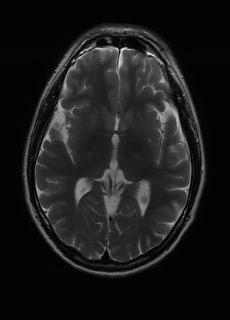

Sequence LR SISO MIMO MIMO tuned GT

λT1=2.61subscript𝜆subscript𝑇12.61\lambda_{T_{1}}=2.61 Refer to caption (a) 34.25/0.9423 Refer to caption (b) 39.24/0.9701 Refer to caption (c) 40.68/0.9821 Refer to caption (d) 41.19/0.9840 Refer to caption (e) PSNR/SSIM

λT2=3.74subscript𝜆subscript𝑇23.74\lambda_{T_{2}}=3.74 Refer to caption (f) 31.80/0.9061 Refer to caption (g) 33.10/0.9687 Refer to caption (h) 33.46/0.9716 Refer to caption (i) 33.59/0.9739 Refer to caption (j) PSNR/SSIM

λflair=5.16subscript𝜆𝑓𝑙𝑎𝑖𝑟5.16\lambda_{flair}=5.16 Refer to caption (k) 28.23/0.8227 Refer to caption (l) 30.34/0.9301 Refer to caption (m) 32.84/0.9396 Refer to caption (n) 35.37/0.9448 Refer to caption (o) PSNR/SSIM

Figure 6: Visual comparison of different recovery methods on simulated data. Note that BraTS sequences are interpolated for registration; therefore the image quality is not as good as the real data.